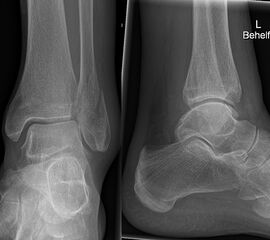

Die Standard-Röntgenaufnahmen des oberen Sprunggelenks bestehen aus drei Aufnahmen: der antero-posterioren Aufnahme (ap), der antero-posterioren Aufnahme mit Innenrotation des Unterschenkels von 20° („Mortise view“), sowie der streng seitlichen Aufnahme (siehe S2-Leitlinie Sprunggelenksfraktur). In der Röntgen-Bildgebung sollte neben den klassischen Frakturzeichen die Integrität der Syndesmose beurteilt werden. Dies erfolgt über die Beurteilung der Breite des lateralen und medialen Gelenkspalts („medial clear space“), des tibiofibularen Abstands 1cm oberhalb des OSG-Gelenkspalts („tibiofibular clear space“), bzw. der tibiofibularen Überlappung. Eine Verbreiterung des tibiofibularen Abstands über 5 mm oder die Erweiterung des medialen Gelenkspalts können Zeichen einer begleitenden Syndesmosenverletzung sein. (Abbildung 3) 6.

Liegt eine Fraktur des oberen Sprunggelenks vor, ist sowohl zur Entscheidung für ein konservatives oder operatives Vorgehen, als auch zur Operationsplanung, ein ausreichendes Verständnis der Fraktur und ihrer Morphologie notwendig. Insbesondere bei komplexen Verletzungen ist dafür die konventionelle Röntgenaufnahme in vielen Fällen nicht ausreichend. So konnten z.B. Black et al. zeigen, dass die operative Strategie zur Versorgung von OSG-Frakturen in 24% basierend auf einer zusätzlichen CT-Bildgebung relevant geändert wurden 7. Dies betraf die Lagerung, die Wahl des Zuganges und die Art der osteosynthetischen Versorgung. Besonders häufig änderte sich das Vorgehen bei Verletzungen des medialen (21%) und des posterioren Malleolus (15%). Darüber hinaus führten dislozierte (dislozierte Frakturen 31% vs. nicht-dislozierte Frakturen 20%) oder komplexe Frakturen (Trimalleolar-Frakturen 29% vs. Unimalleolar-Frakturen 10%) besonders häufig zu relevanten Änderungen des operativen Vorgehens. Die Computertomographie ist daher, insbesondere bei Bi- und Trimalleolar-Frakturen, essentiell für das Verständnis der Fraktur und somit für die Planung und Durchführung der Operation. In Abbildung 4 und 5 sind exemplarisch ein Röntgen- und ein CT Befund gegenübergestellt.